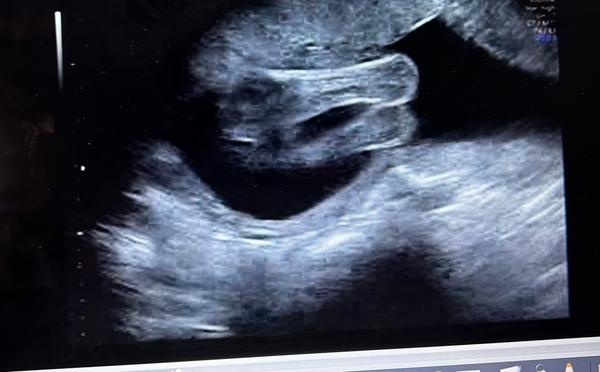

chtěla bych se zeptat na pohlaví miminka. 🙂

z fotografií nelze jednoznačně říci. ☹ Výpovědní hodnotu vyšetření "naživo" fotografie nedokáží nahradit.